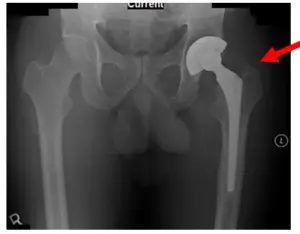

El paciente es un varón de 70 años que acudió con dolor intenso en la cadera izquierda tras haberse sometido a una artroplastia total de cadera izquierda (ATC) hace varios años. En la visita inicial, las radiografías mostraban signos de osteólisis periprotésica del vástago femoral y un leve engrosamiento de la cortical distal. También se observa el aflojamiento de la prótesis, junto con el pedestal en el extremo distal. A continuación se muestran las radiografías.

Radiografías de la cadera izquierda antes de la revisión de la ATC izquierda en septiembre de 2011